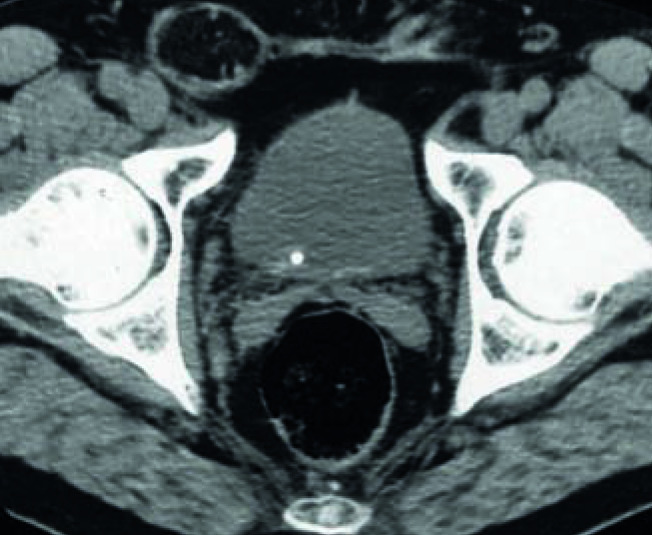

L’URS est réalisée avec des urétéroscopes métalliques de 2-3 mm de diamètre permettant d’accéder à l’uretère. L’URSS est pratiquée avec des urétéroscopes souples, fibrés ou numériques, de moins de 3 mm de diamètre atteignant les cavités rénales par voie rétrograde afin d’extraire le calcul à la pince. Associées à la fragmentation par laser, elles sont très efficaces sur ceux de moins de 2 cm, quelles que soient leur composition et leur densité au scanner (fig. 3 et 4).2-6 En effet, aucun ne résiste à l’application intracorporelle d’un laser, même si ceux dont la taille avoisine les 2 cm requièrent parfois 2, voire 3 séances. Un drainage par sonde JJ est souvent laissé en place en post-opératoire.

La NLPC consiste à introduire un néphroscope dans le rein à travers la paroi postérieure de l’abdomen par un tunnel mesurant 5 à 10 mm de diamètre. La fragmentation, effectuée par procédé endocorporel (laser ou ultrasons) est suivie de l’extraction. C’est le traitement de référence des calculs volumineux, supérieurs à 2 cm, et plus généralement complexes et coralliformes (fig. 5 et 6).